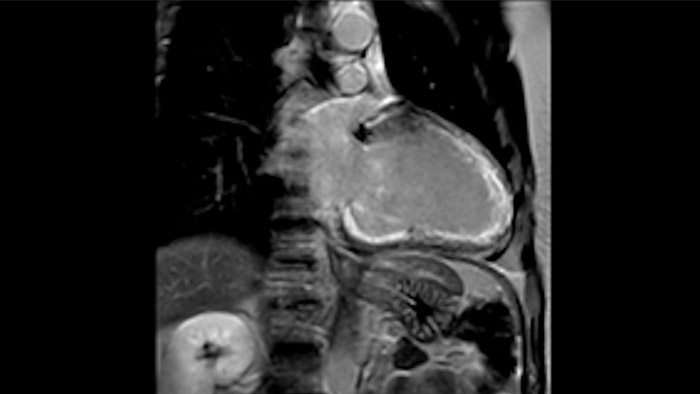

IntelliSpace Portal MR Caas5,6 4D Flow è una soluzione di post-elaborazione che consente di generare ricostruzioni volumetriche 3D per visualizzare e valutare il flusso di sangue in strutture cardiovascolari come le valvole cardiache, le camere e i vasi in base alle immagini MR 4D Flow.

L'utilità diagnostica e prognostica della RM cardiaca è in continua crescita. È possibile valutare l'anatomia e la funzionalità cardiache utilizzando acquisizioni cine, ottenere informazioni sulla perfusione e vitalità del tessuto cardiaco, visualizzare potenziali edema con la sequenza Black Blood, accedere e persino quantificare la caratterizzazione dei tessuti con CardiacQuant.